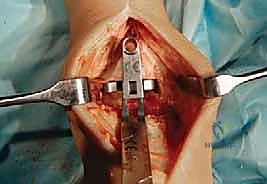

تُجرى العملية عادة تحت التخدير العام أو التخدير النصفي (الشوكي). يقوم د. هطيف بعمل شق جراحي أمامي أو جانبي (حسب التقنية المستخدمة وحالة المريض) للوصول إلى مفصل الكاحل بعناية، مع الحفاظ على الأوتار والأعصاب والأوعية الدموية المحيطة.

3. إزالة الأسطح التالفة (تحضير العظام)

باستخدام أدوات جراحية دقيقة وموجهات خاصة، يتم إزالة الغضاريف التالفة وجزء رقيق جداً من العظام المريضة من نهايتي عظمة الظنبوب وعظمة الكاحل (Talus). يتم تشكيل العظام بدقة لتتطابق تماماً مع شكل أجزاء المفصل الصناعي.